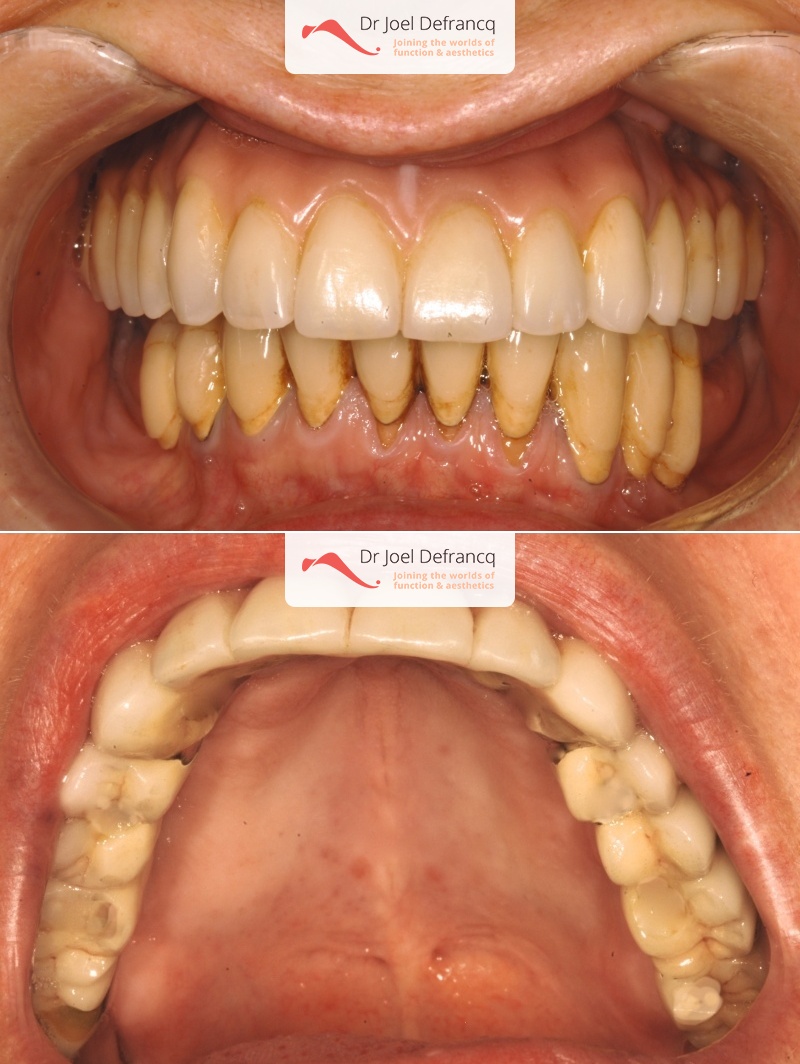

Bieke

Dentale diagnose

- Klasse I

Behandeling tandheelkundige implantaten

- Vaste tanden op implantaten (bovenkaak)